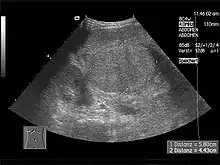

L'échographie abdominale montre un parenchyme hépatique hétérogène et nodulaire, contours bosselés, avec une hypertrophie du segment I ou lobe caudé, des signes d'hypertension portale avec augmentation de la taille de la rate (splénomégalie)…